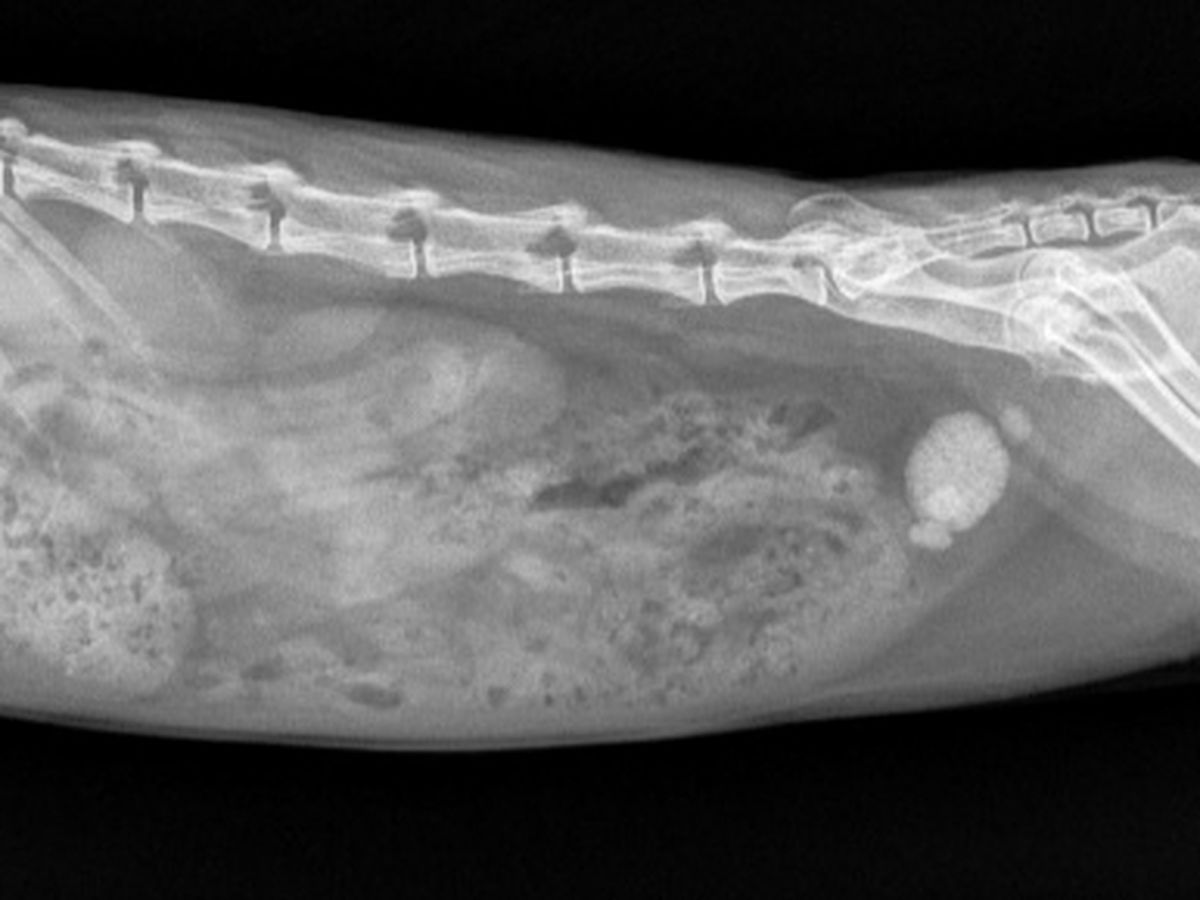

To all the Animal lover, please help my little sookie to have surgery. Its an emergency surgery for her. She has kidney stone and we need your help, even if its a $1 that count,we love her so much & if we dont do the surgery the only option is euthanasia